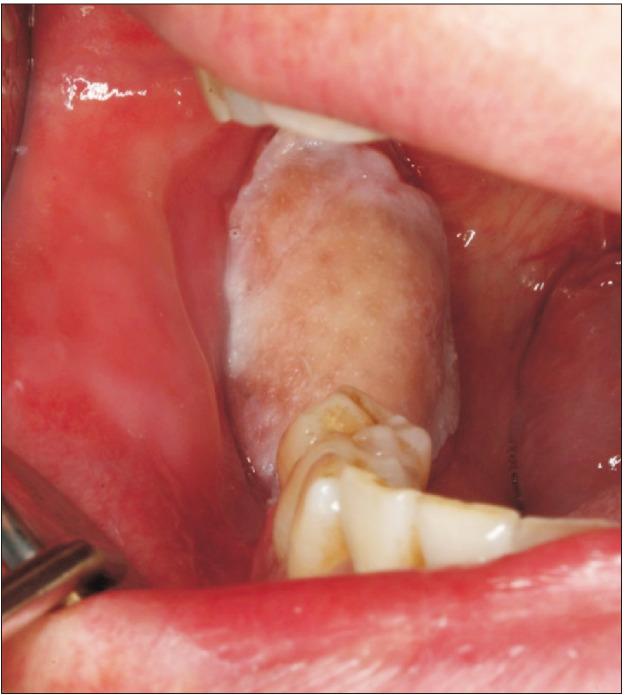

Primary intraosseous squamous cell carcinoma (PIOSCC) is very rare type of squamous cell carcinoma (SCC) that occurs within the jaw and arises from remnants of odontogenic epithelium with no connection to the oral mucosa. This study reports two cases of PIOSCC of the mandible. Reported in this article are two cases of PIOSCC of the mandible that were treated with resection and reconstruction using a fibular free flap. The first case was a 36-year-old male patient who complained of right mandibular pain. Computed tomography (CT) and panoramic radiograph revealed a large radiolucency in the mandibular ramus area. At first, an odontogenic keratocyst was tentatively diagnosed, and an excision procedure was carried out at another clinic. A final biopsy after cyst enucleation revealed well-differentiated SCC, so we proceeded with segmental mandibulectomy and reconstruction using a fibular free flap. The second case was a 48-year-old male patient with left mandibular pain. CT and panoramic radiograph revealed irregular radiolucency in the mandibular angle area near tooth #38. At first, osteomyelitis was tentatively diagnosed, and a curettage was carried out. A later biopsy revealed well-differentiated SCC, so segmental mandibulectomy and reconstruction with a fibular free flap were secondarily performed. Our two cases have had no recurrence. The facial appearance of both patients is satisfactory, and the neo-mandibular body created using a fibular bone transfer displays adequate bony volume.

原发性骨内鳞状细胞癌(PIOSCC)是一种非常罕见的鳞状细胞癌(SCC),发生于颌骨内,起源于牙源性上皮残余,与口腔黏膜无连接。本研究报告了两例下颌骨PIOSCC病例。本文报道了两例下颌骨PIOSCC病例,采用游离腓骨瓣进行切除和重建治疗。第一例是一名36岁男性患者,主诉右下颌疼痛。计算机断层扫描(CT)和全景X线片显示下颌支区域有一个大的透射区。起初,初步诊断为牙源性角化囊肿,并在另一家诊所进行了切除手术。囊肿摘除后的最终活检显示为高分化SCC,因此我们进行了下颌骨节段性切除并用游离腓骨瓣进行重建。第二例是一名48岁男性患者,有左下颌疼痛。CT和全景X线片显示38号牙附近下颌角区域有不规则透射区。起初,初步诊断为骨髓炎,并进行了刮除术。后来的活检显示为高分化SCC,因此二期进行了下颌骨节段性切除并用游离腓骨瓣进行重建。我们的两例病例均无复发。两名患者的面部外观均令人满意,使用腓骨骨移植构建的新下颌体显示出足够的骨量。